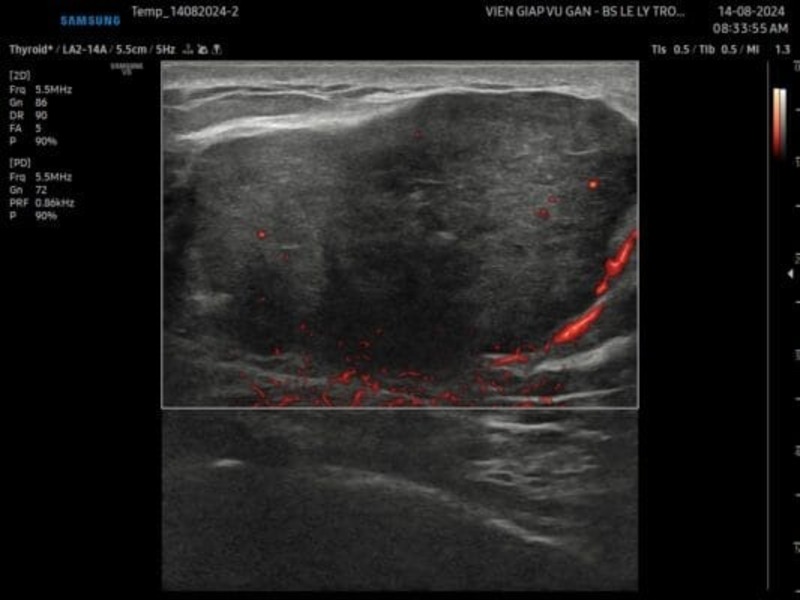

HÌNH 2: Trên siêu âm vi mạch ghi nhận mạch máu phân bố chủ yếu ở ngoại vi, mạch máu bên trong rất ít